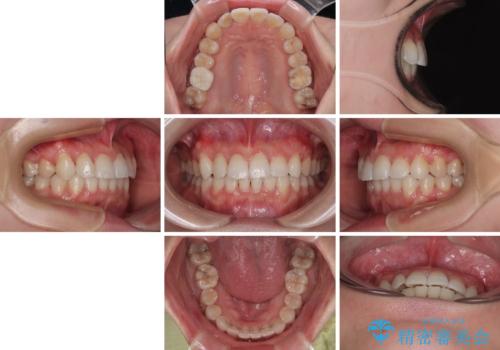

捻転の強い前歯 ワイヤー装置での非抜歯矯正

- 前歯のデコボコ、特に90度捻れている上顎前歯を気にして来院された患者様です。

マウスピースでもワイヤーでも対応可能でしたら、捻転が非常に強いことから、患者様と相談の上ワイヤー装置にて矯正治療を行うこととしました。

捻転を解消する際に、歯列全体が前方に突出して出っ歯の仕上がりとなることが懸念されたため、補助装置を用いて上顎歯列全体を後方に移動する力をかけることとしました。

当初予定通り1年半ほどの治療期間で、非常に綺麗な歯列に仕上げることができました。